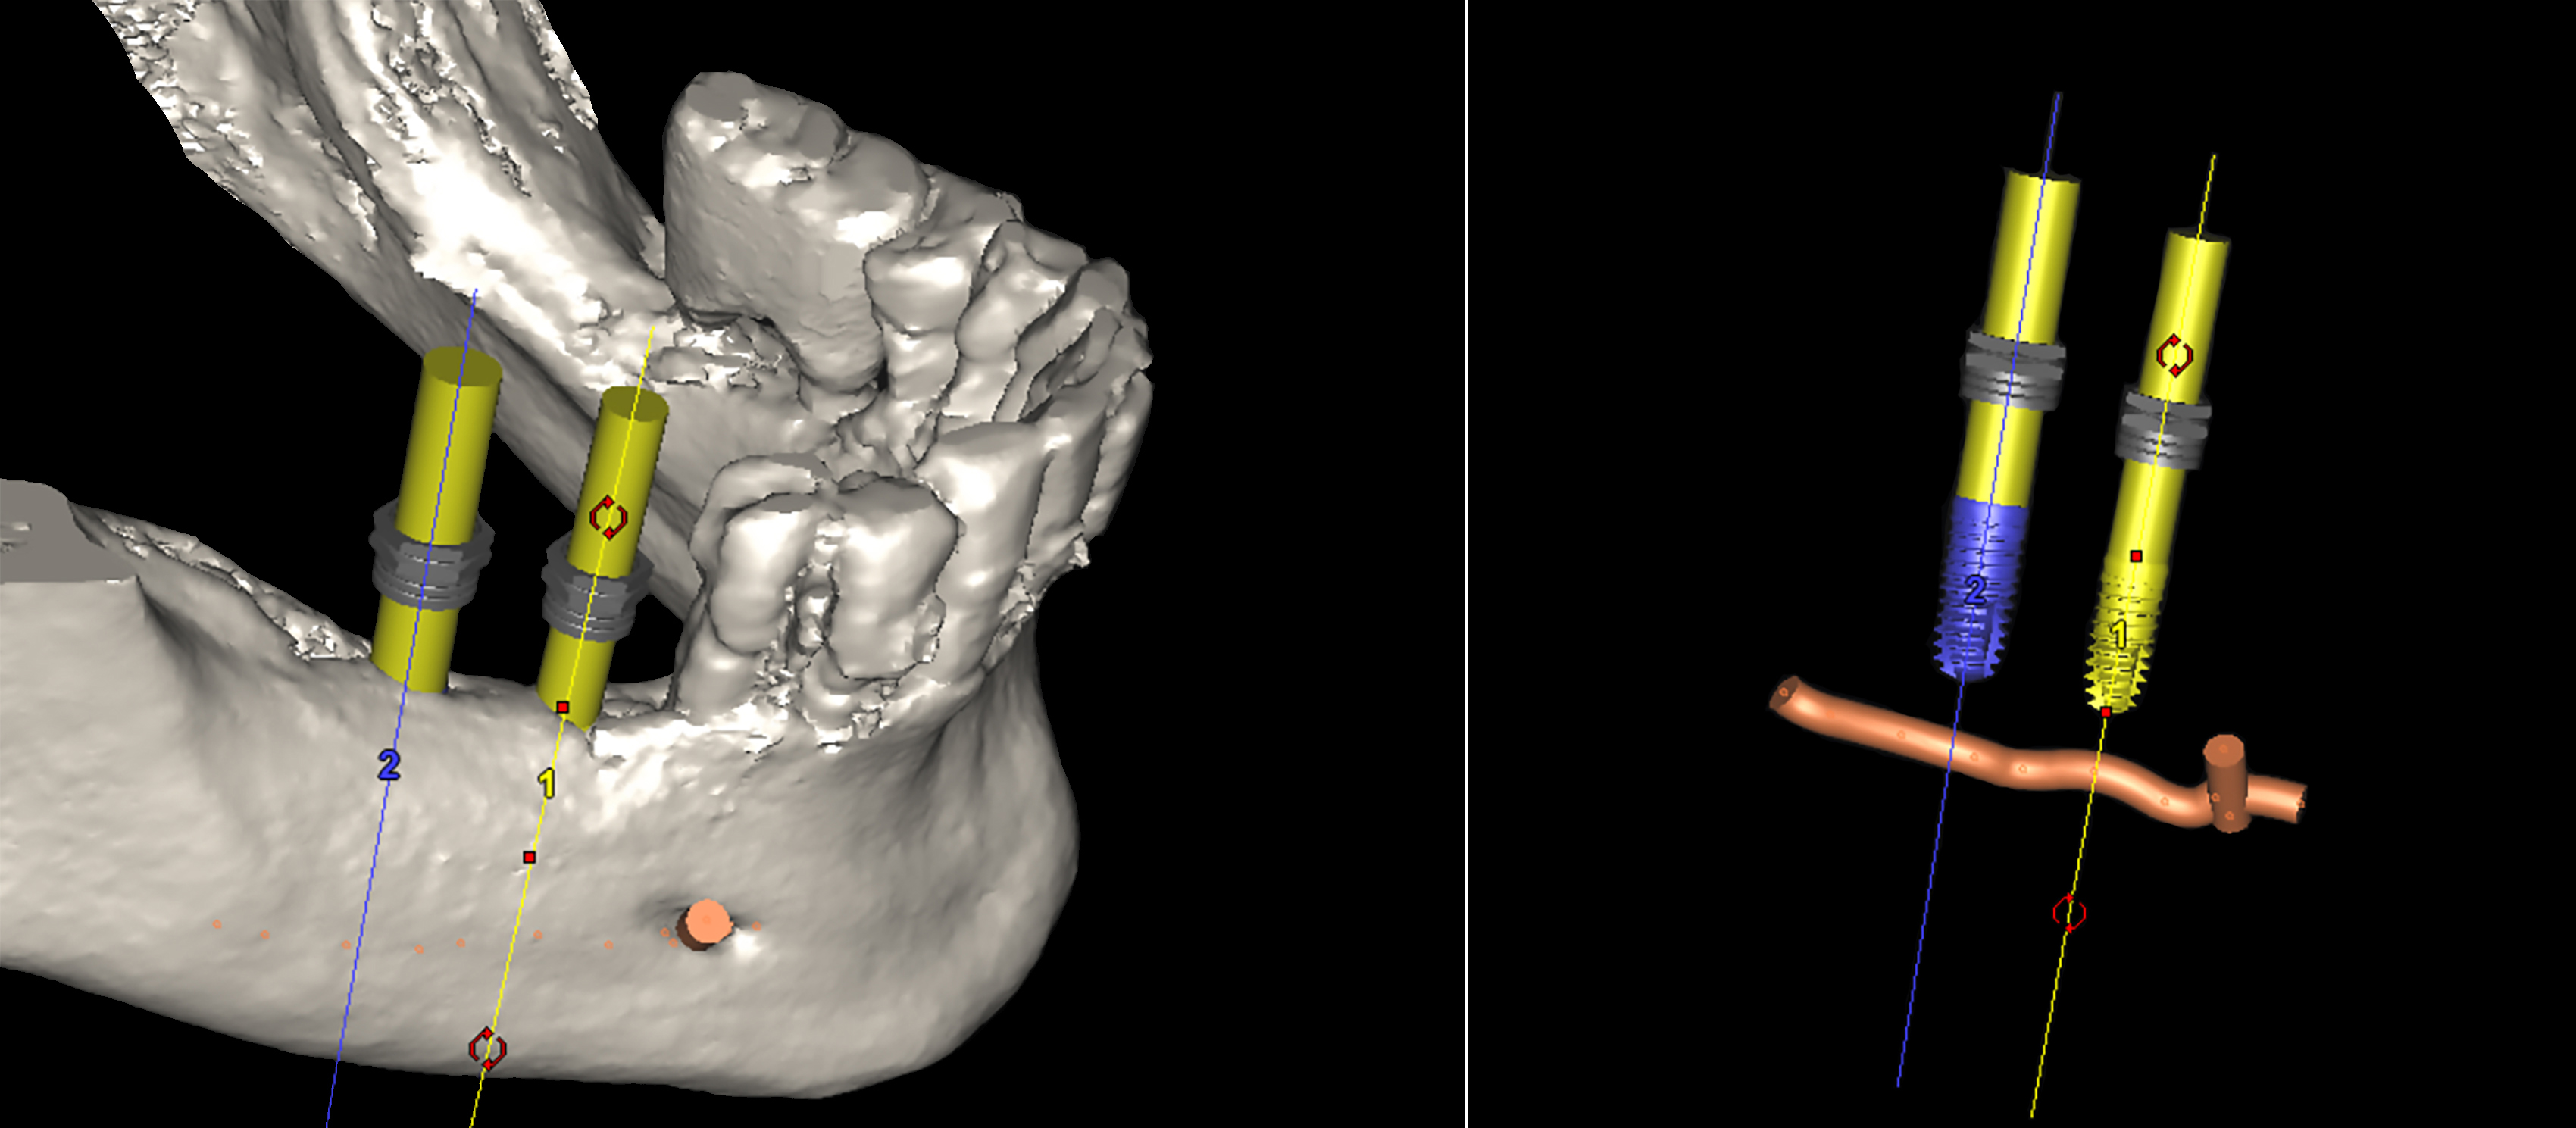

3D αξονική τομογραφία – Πανοραμική και εγκάρσια τομή της κάτω γνάθου της ασθενούς - Η τοποθέτηση των δύο εμφυτευμάτων έγινε στις ιδανικότερες θέσεις, με τη βοήθεια εξειδικευμένου λογισ�μικού χειρουργικού σχεδιασμού που χρησιμοποιούμε για την ακρίβεια και την ασφάλεια κάθε εμφυτευματικού περιστατικού

3D αξονική τομογραφία – Εγκάρσιες τομές της κάτω γνάθου της ασθενούς.

Απεικονίζονται τα δύο εμφυτεύματα που τοποθετήθηκαν με τη βοήθεια εξειδικευμένου προεγχειρητικού λογισμικού. Μέσω της ανάλυσης μπορούμε να αξιολογήσουμε τη θέση τους στο οστό, τον προσανατολισμό και τις μεταξύ τους κλίσεις, καθώς και την πιθανή γειτνίασή τους με σημαντικά ανατομικά μόρια

3D αξονική τομογραφία – Αριστερά: τρισδιάστατο μοντέλο του οστού της κάτω γνάθου με ψηφιακά τοποθετημένα τα δύο εμφυτεύματα.

Δεξιά: το ζωτικής σημασίας κάτω φατνιακό νεύρο και τα ψηφιακά ομοιώματα των εμφυτευμάτων. Η απόσταση από το νεύρο είναι επαρκής, επιτρέποντας την ασφαλή τοποθέτησή τους

Με βάση την CBCT της κάτω γνάθου, προχωρήσαμε στον εικονικό σχεδιασμό των εμφυτευμάτων μέσω ειδικού προεγχειρητικού λογισμικού. Αξιολογήθηκε το ύψος, το πάχος και η ποιότητα του οστού, καθώς και η σχέση με κρίσιμες ανατομικές δομές όπως το κάτω φατνιακό νεύρο.